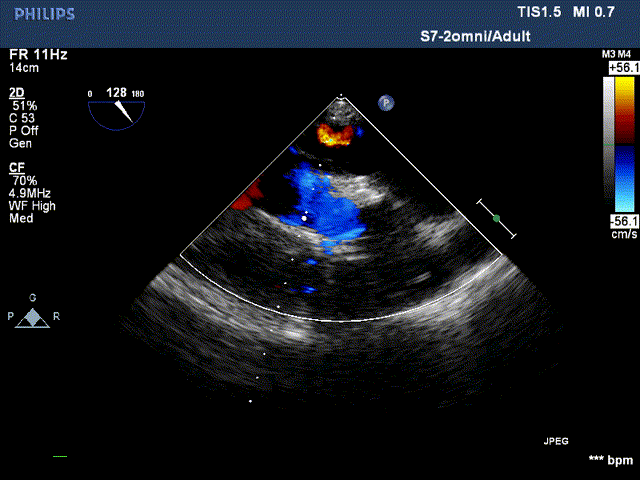

术后超声:

术后超声提示:无瓣周漏,血流动力学明显改善,二尖瓣重度反流改善为轻度反流。

跨瓣压差:

术前跨瓣压差96mmHg,术后跨瓣压差2mmHg。